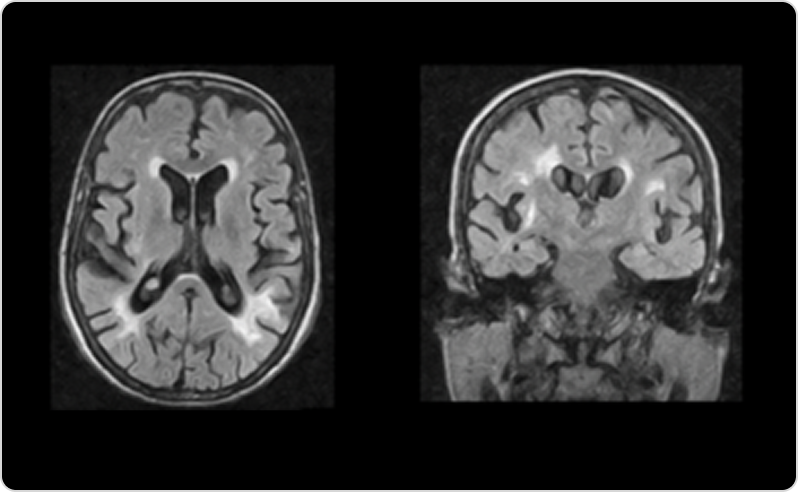

• МРТ-да анықталатын мидың ақ затының зақымдануы — созылмалы тамырлық зақымданудың белгісі.38

Фабри ауруы кезіндегі өзгерістері бар ми МРТ-сі

3-сурет. Фабри ауруы бар 40 жастағы әйелдегі Т2-салмақталған МРТ кескіндерінде ақ заттың екіжақты диффузды, дақты және ішінара қосылатын гиперинтенсивті ошақтары.

Дереккөзден бейімделген: Cocozza S et al. Insights Imaging. 2018;9(6):1077–1088. © The Author(s) 2018. CC BY 4.0.42